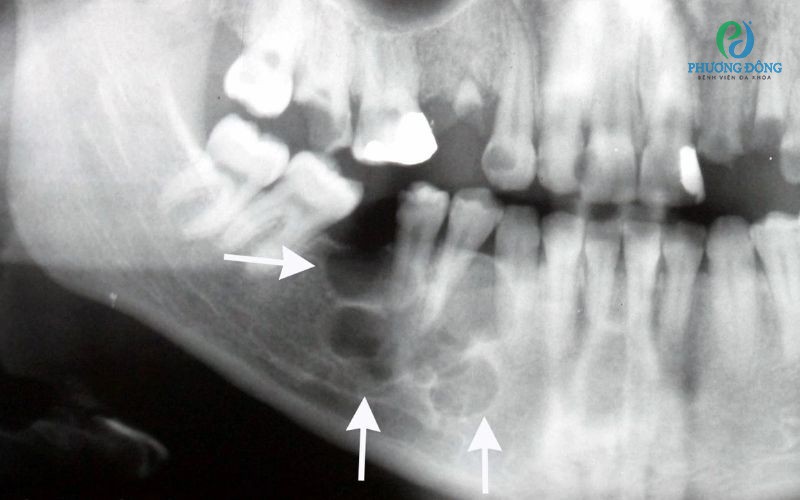

• U men thể nang: Đây là loại u phổ biến nhất, thường xuất hiện ở xương hàm dưới và có liên quan đến các vấn đề về răng.

• U men răng: Khối u có nguồn gốc từ tế bào tạo men, phát triển chậm và có khả năng xâm lấn các mô xung quanh.

• Nang thân răng: U nang hình thành từ các mô răng, có thể từ các vấn đề về răng miệng.

Giai đoạn khối u làm biến dạng xương

Ở giai đoạn này, người bệnh xuất hiện tình trạng vùng xương hàm bị phồng bề mặt cong, đồng thời có cảm giác nặng nề. Có một số trường hợp có thể có dị cảm hoặc mất cảm giác tạm thời do khối u chèn ép dây thần kinh.